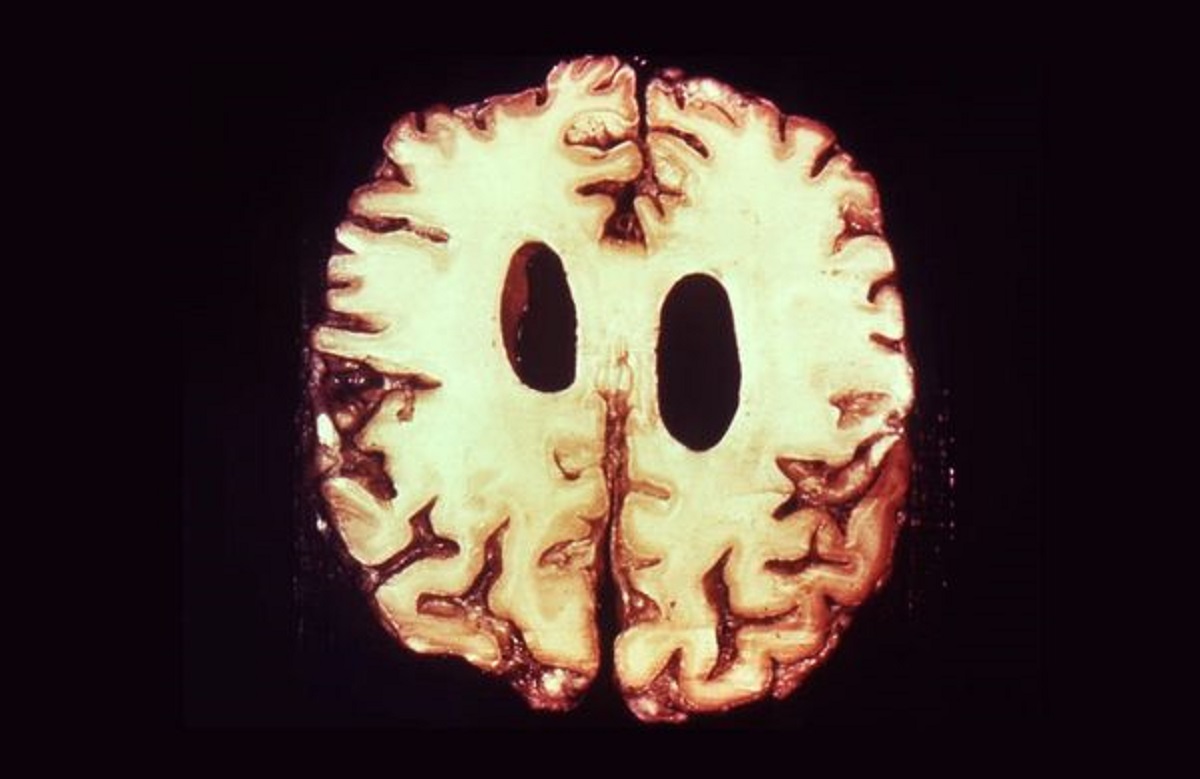

Años después de la infección inicial, algunos pacientes desarrollaban neurosífilis: una forma avanzada que afectaba el cerebro. Podía provocar convulsiones, alteraciones mentales profundas y deterioro cognitivo progresivo. No había cura. Solo espera.

Hoy sabemos que la sífilis no es causada por un virus, sino por una bacteria llamada Treponema pallidum. En aquel momento, el conocimiento era limitado, pero la observación clínica llevó a intentar esta estrategia.